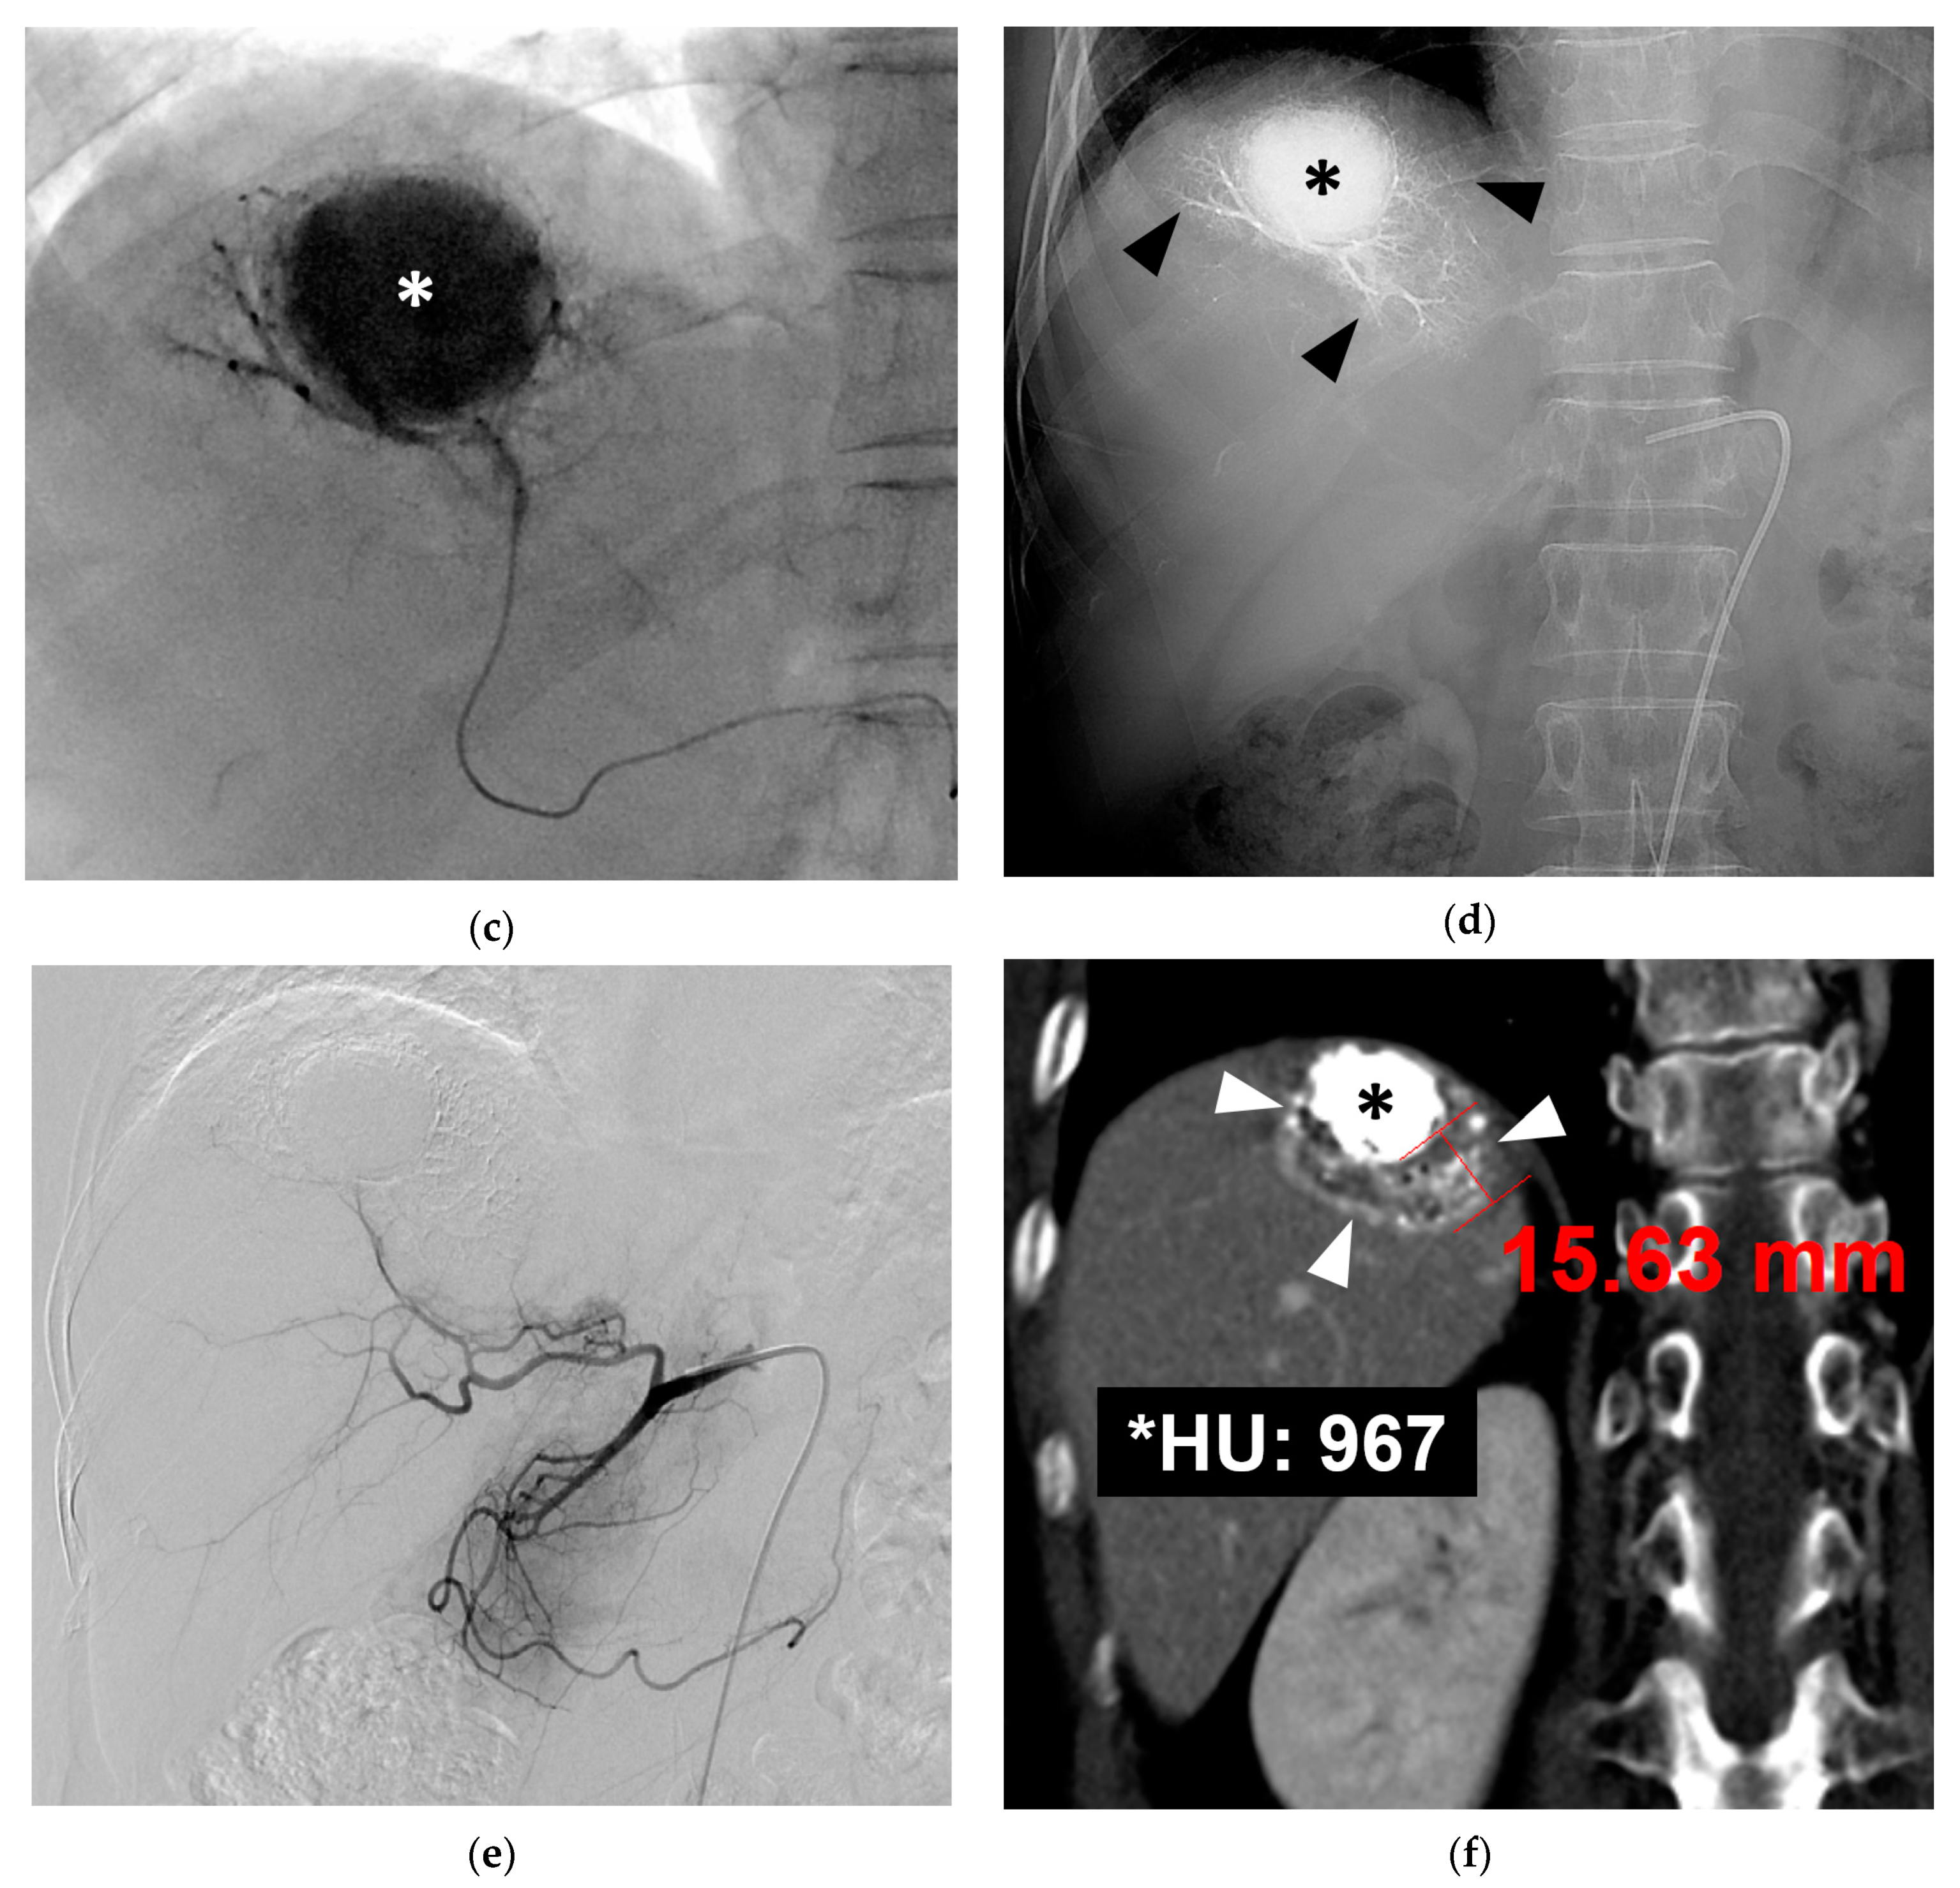

3.1. B-TACE Procedure and Complications

3.2. Follow-Up

3.3. Local Recurrence

3.4. Overall Survival and Post-Recurrence Survival